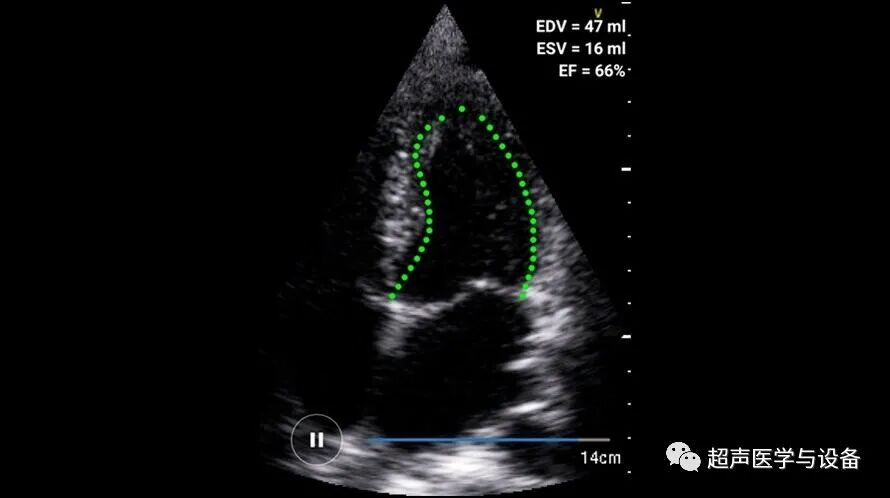

同时它“简约而不简单”,它是少有的采用自动优化Vspeckle斑点噪声抑制、二维声束偏转技术、梯形成像技术、全景成像技术、 中位线穿刺引导技术、穿刺针增强技术、左室心内膜自动描记Auto EF等众多高级功能的掌上超声!可实现腹部、妇产科、浅表组织、小器官、外周血管、泌尿科、ICU、麻醉科、急诊、介入等全身应用。

iM10支持二维码扫描新建病人信息来更高效快捷的输入病人信息帮助医生减少输入时间,并且更加准确与全面。针对不同部位个性化参数预设,专机专用,无需重复调节参数,初学者也轻松上手。同时它内涵丰富,具备PW自动测量与评估功能、IMT自动测量与评估功能、脂肪自动测量与评估功能、穿刺针针尖增强功能等高级功能,堪称“掌超界的杠把子”!